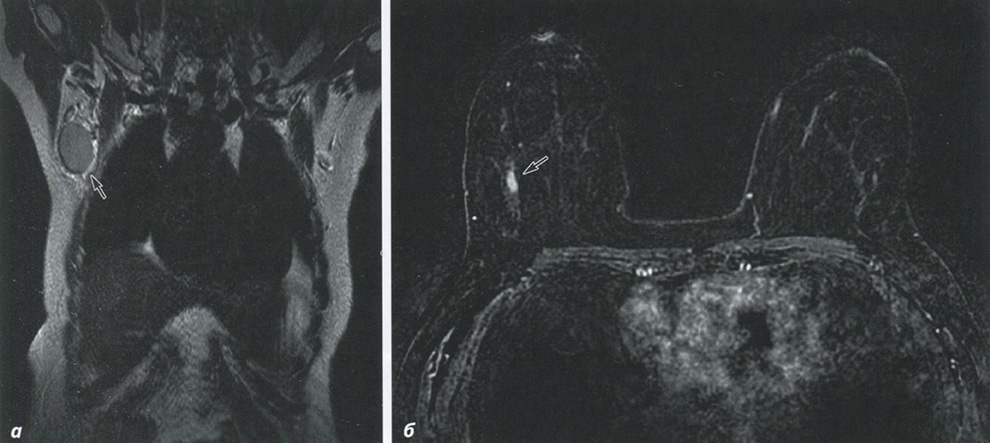

Магнитно-резонансная томография позволяет получать высококачественные изображения мягких тканей, что делает её идеальным инструментом для диагностики опухолей различного происхождения. Использование контрастных средств дополнительно улучшает визуализацию, позволяя врачам получить более четкую картину о размерах и локализации опухоли. Исследования показывают, что применение нового поколения контрастных веществ, а также усовершенствованные алгоритмы обработки изображений, значительно увеличивают точность диагностических заключений.

Контрастные вещества в данном контексте выполняют функцию "сигнального усилителя", благодаря чему опухоли проявляются более ярко на изображениях. Это дает возможность не только обнаружить опухоль, но и оценить ее васкуляризацию, плотность и другие важные характеристики, которые могут повлиять на выбор стратегии лечения. Применение таких технологий открывает новые горизонты в онкологии, позволяя врачам делать более обоснованные выводы.